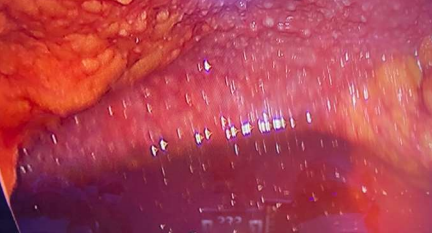

Due to lack of conclusive tissue diagnosis of cancer, chemotherapy could not be started even though the clinical picture was highly suggestive. She underwent assessment laparoscopy (which in the presence of gross ascites is a challenge), to assess feasibility for debulking surgery and obtain tissue diagnosis. Intra-operatively there was large volume ascites (more than four litres was drained), innumerable nodular deposits (0.5cm size) over all intra-abdominal organs and peritoneal surfaces, clumping of the bowels and omentum. (Fig 2) Biopsies were taken from accessible organs (ovary, endometrium, omentum) and peritoneal reflections of various sites and sent for frozen section. None of the samples showed conclusive evidence of malignancy, however, biopsy from the ovary revealed a solitary epithelioid cell granuloma. Ascitic fluid picture was exudative with lymphocytosis. Final biopsy report of all sites showed several Langhan's type of giant cells within granulomas, with central caseous necrosis. Final diagnosis was granulomatous oophoritis & granulomatous inflammation. With this she was started on definitive treatment with four drug ATT regimen and made uneventful recovery. At six month follow up, her CA-125 is in the normal range and there is no evidence of ascites on ultrasound. Incidentally, her AFB culture at six weeks was negative.

Fig 2: Laparoscopy image with gross ascites, nodular deposits in omentum & peritoneum (laparotomy was avoided

The intra-operative picture was of diffuse sub-centimetre nodules over all peritoneal and organ surfaces, and can be seen in both peritoneal carcinomatosis and miliary peritoneal tuberculosis. The final diagnosis was secured by finding no malignant cells and instead finding typical granulomatous inflammation on the peritoneal nodules sent for frozen section analysis. Peritoneal TB may be wet type with massive ascites, fibrotic fixed type with matted bowel and omental masses, or dry type with dense adhesions. Wet type is the most common5 and this patient had a mixture of the wet and fibrotic type of disease.